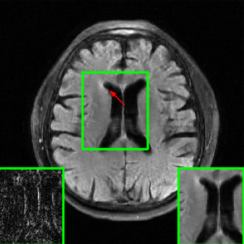

Figure 1 illustrates reconstructed images from the instabilities and the generalization challenges considered in this paper.

| PSNR = 30.8 dB | PSNR = 23.21 dB | PSNR = 22.18 dB |

| (a) | (b) | (c) |

| PSNR = 24.15 dB | PSNR = 27.26 dB |

| (d) | (e) |